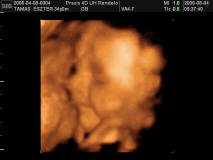

Tamesz

Nagyon aranyos,dundi arcú a Lili kisasszony!